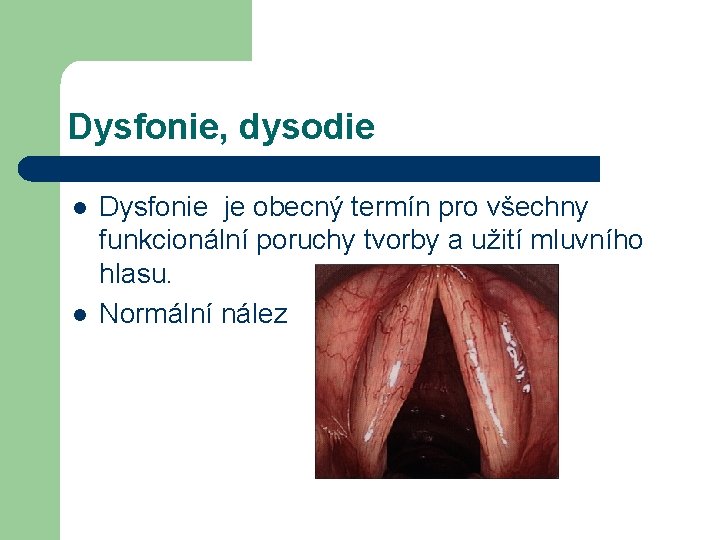

Dysfonie, dysodie l l Dysfonie je obecný termín pro všechny funkcionální poruchy tvorby a užití mluvního hlasu. Normální nález